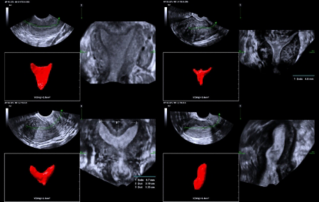

Ultrasound Journal 34 - Use of IOTA-ADNEX & O-RADS risk assessment models in MDT management of Adult Granulosa Cell Tumor

Comprehensive overview of granulosa theca cell tumors of the ovary, covering epidemiology, clinical presentation, diagnosis, treatment options, and prognosis for both adult and juvenile types.